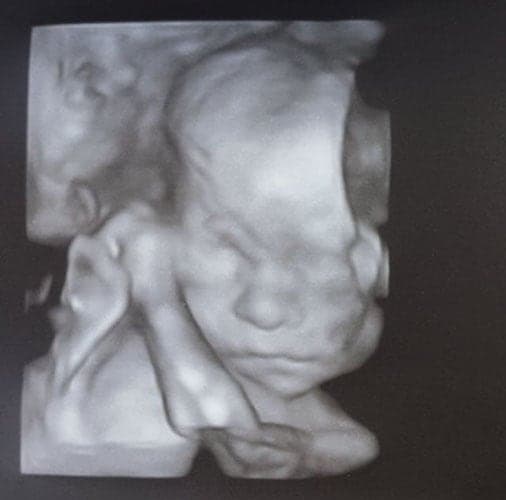

Ultraschallbilder aus dem 3. Trimester (29. bis 40. SSW)

Im dritten Trimester der Schwangerschaft ist das Baby so groß, dass es nicht mehr komplett auf ein Ultraschallbild passt. Nun kann man wunderbare 3D-Ultraschalle des Gesichts machen. In diesem Semester nehmen die Babys nochmal rasant zu und wer Glück hat, kann auf seinem Ultraschall schon erste Gesichtszüge erkennen.